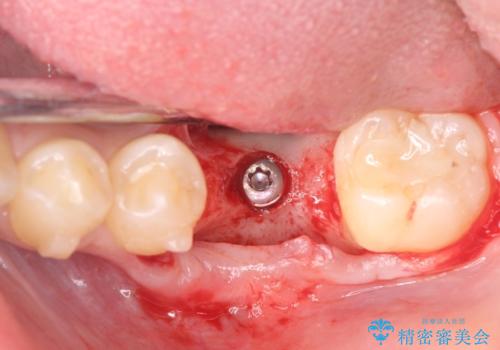

割れてしまった奥歯は抜歯し、矯正治療中の良いタイミングでインプラントを埋入することとしました。

インプラントは、治療期間を短くすることが可能な、ストローマン社のSLActiveを使用することとしました。